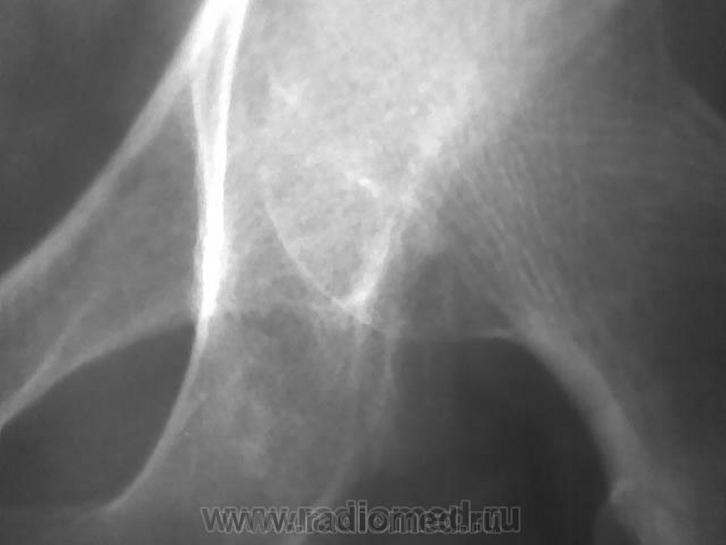

Неоднородность структуры седалищной кости за счет нечетких просветлений. В первую очередь, заподозрила бы мтс. На дополнительных изображениях вроде мягкотканный компонент по нижней границе суставной капсулы. Хотелось бы сравнительное изображение обоих суставов да и верхней/3 бедер

Не исключая остеолитический метастаз все же складывается мнение о суммации теней мягкотканного компонента, вот почему и было высказано мнение о пахово-мошоночной грыже.

Может пусть хирург пахово мошоночную грыжу поищет?.....

Остеолитический МТС?